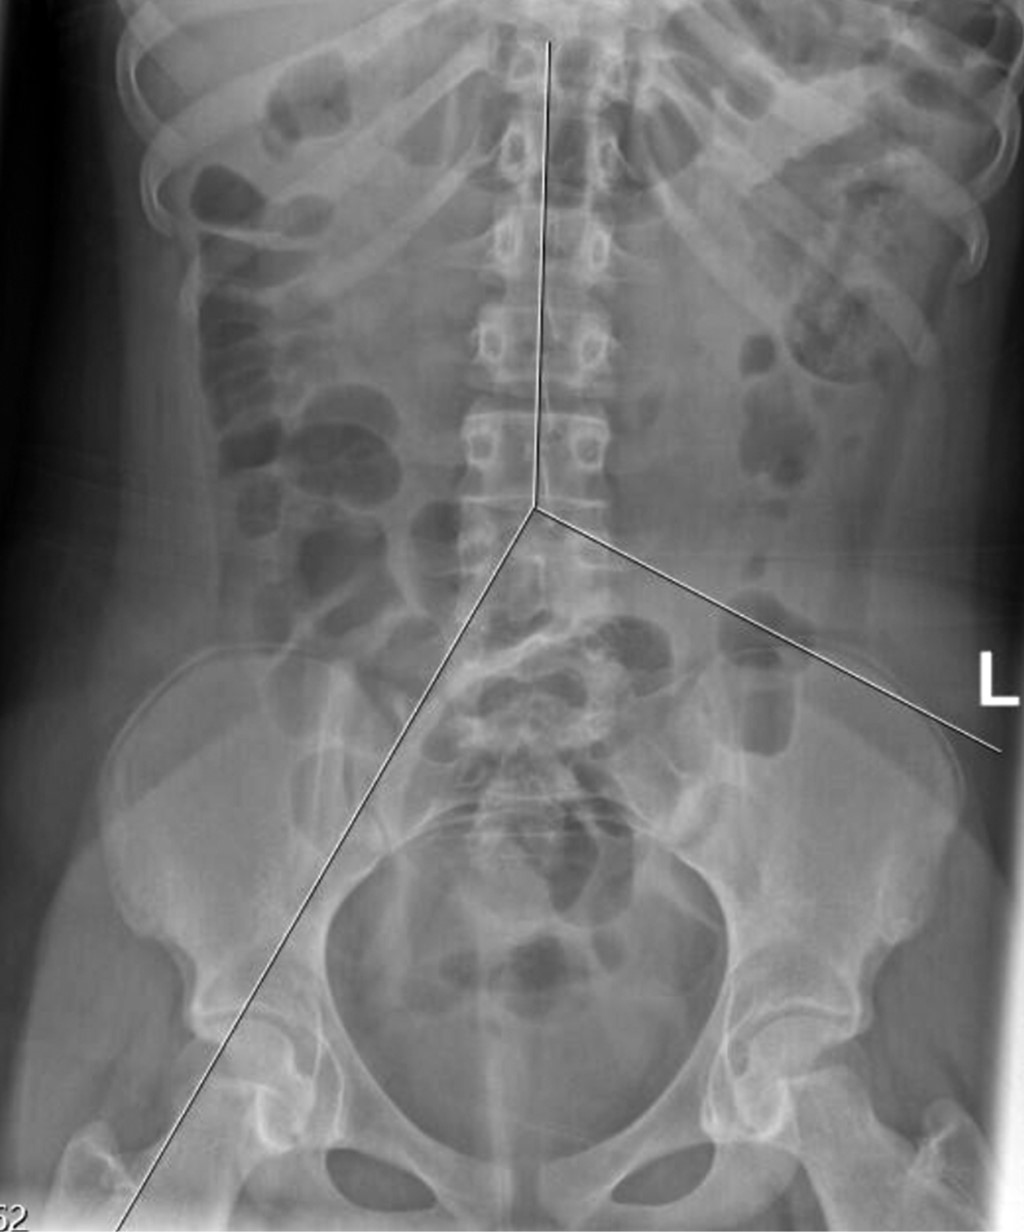

Para determinar el subtipo de estreñimiento funcional se estableció el sitio donde se encontraban al menos dos de los 10 marcadores radiopacos (zona positiva). Para establecer el sitio anatómico de los marcadores se trazaron tres líneas sobre la radiografía abdominal: una vertical sobre las apófisis espinosas de las últimas vértebras torácicas hasta la quinta lumbar (L5), otra oblicua desde el cuerpo vertebral de L5 hasta la parte superior del fémur derecho, y una tercera línea horizontal, del borde superior de la vértebra L5 hasta la espina iliaca anterosuperior izquierda (Figura 2).

Las tres líneas delimitaron tres áreas: el colon derecho entre las líneas 1 y 2; el colon izquierdo entre las líneas 1 y 3, y el recto sigmoides por debajo de las líneas 2 y 3. Si los marcadores se encontraron en el colon se consideró un estreñimiento por "inercia colónica"; en la zona del sigmoides como asociado con "alteración del piso pélvico". En caso de que los marcadores se identificaran en más de una zona se consideró como causa mixta, y cuando se determinó la ausencia de marcadores, el diagnóstico fue de "estreñimiento funcional o de tránsito normal".